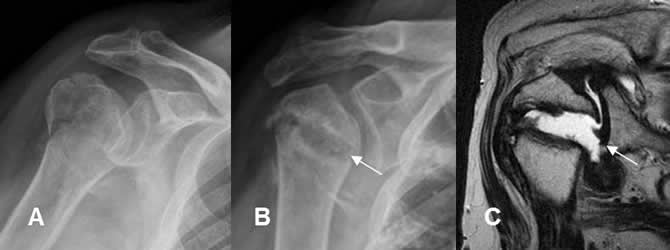

Fig 132. Osteonecrosis del escafoides.

A: Rx AP, B: TAC reconstrucción coronal y C: TAC reconstrucción sagital. Fractura del escafoides fijada con material de osteosíntesis. El polo inferior es denso y ha perdido volumen, por osteonecrosis. (Flechas gruesas). Adicionalmente hay signos de seudoartrosis, con aumento del espacio entre los extremos, esclerosis de los bordes y ausencia de callo óseo. (Flecha delgada).